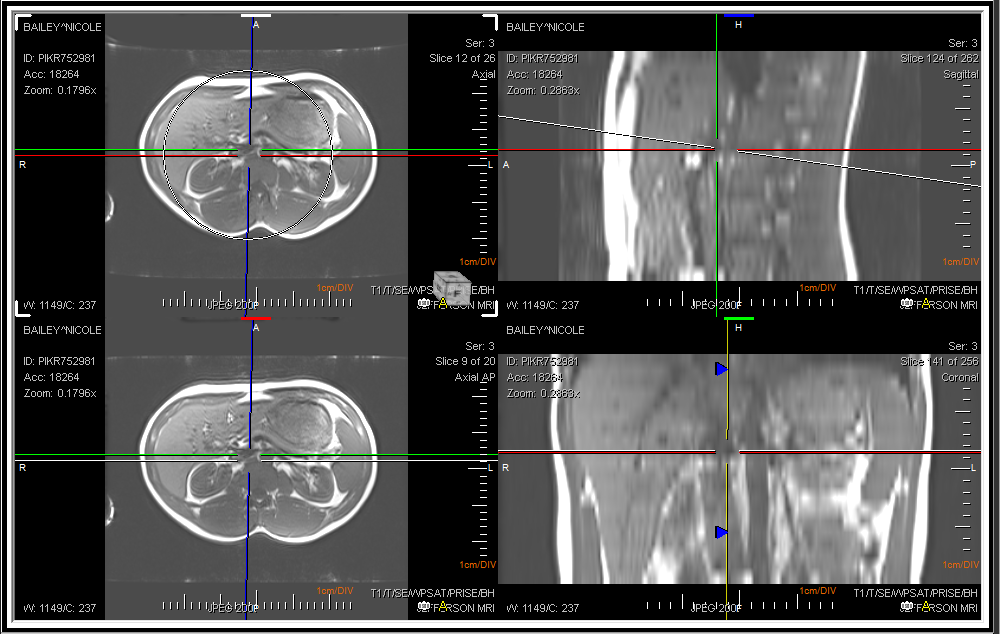

At any given time, one of the Viewports can be selected as the Controlling viewport with a click of a mouse. The remaining three view boxes display the cutting planes related to the three axes in the controlling viewport. All three axes are joined in the center. The Oblique option allows the X and Y axis to rotate. If this option is checked off, the user will not be able to move the axis. The option is checked by default. The horizontal and vertical axes are perpendicular to each other and make up the double cutting plane. The third axis is independent of the other two axes and can be rotated around the center point, calle the single cutting plane. As the cutting planes are rotated and translated, the remaining three view boxes update to reflect the new cuts. While the Vertical axis is used to rotate the image across the y-axis, two slide bars at the right hand and at the bottom of the image can be used.

The MPR mode allows to view the image in three views i.e. Axial, Coronal or Sagittal. If the user wishes to perform an operation on the image in one view, the change will be visible in all the three views simultaneously. To scroll through images, simply use the central wheel button of the mouse.

While in MPR mode, a limited set of tools are available from PowerReader which can be used to modify the images within the view boxes. The user can Select, Drag, Zoom, Pan and Window/Level the image. The users can choose to invert the image, Mirror or rotate the image. There is also the option to Measure Tool, Measure Angle, Point of Interest, Annotation Text and use the Region of Interest (ROI) tools. The Create Path tool can be used to show a step by step snapshot of the image at specific 3D points. The Create path tool is described in detail in the section How Do I Create a Path in 3D MPR.